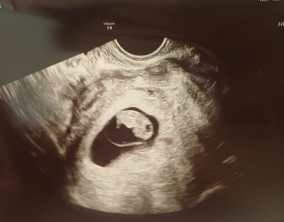

설렘과 불안의 시간을 지나 찾아온 선물

서울IVF여성의원의 난임 치료는 과정 하나하나가 체계적이고 세심하다는 인상을 받았습니다. 이유정 원장님과 간호사 분들께 치료 단계마다 충분한 설명을 들을 수 있어 불안이 많…